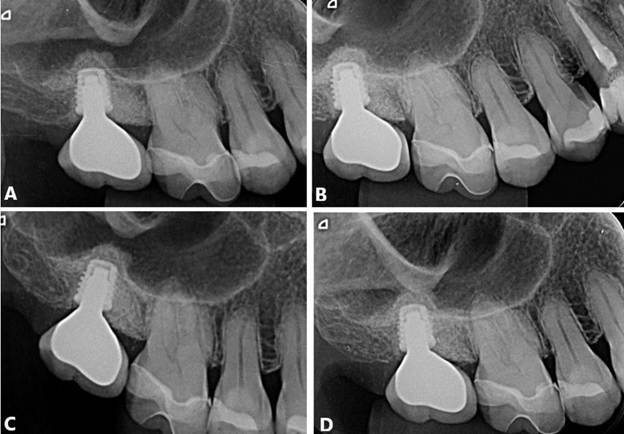

Paciente Y. S. K, sexo masculino, 65 anos de idade, compareceu ao consultório particular queixando-se do elemento 17. O paciente relatou ausência de histórico de alterações sistêmicas e de alergias. Após avaliação clínica e radiográfica (Figura 29, A – D), o tratamento consistuiu por exodontia do 17, devido à fratura e inviabilidade de manutenção, e reabilidação com implantes dentários. Inicialmente, a exodontia foi realizada, concomitantemente a preservação alveolar utilizando enxerto Cerabone (Straumann, Villeret, Suíça) e membrada de politetrafluoroetileno (PTFE). Após um período de 21 dias, a membrana foi removida (Figura 30. A,B). Segui-se pela instalação de implante curto ARCSYS (FGM, Joinvile – SC, Brasil) 4,3 mm x 5,0 mm na região do 17. O acompanhamento radiográfico foi realizado, com resultado clínico e radiográfico satisfatório (Figura 31. A – D).

Figura 29. A – D) TCFC da região do 17.

Figura 31. A) Radiografia final em set/2018. B) Set/2029. C) Mai/2019. D) Set/2019.